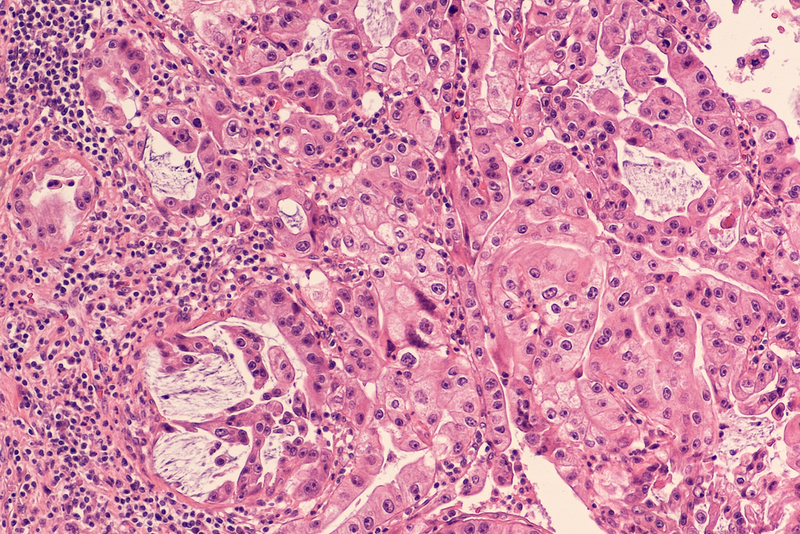

Pancreatic cancer is resistant to all current treatments. Patients have extremely poor chances of surviving for five years after being diagnosed but a new study found that a small molecule has the ability to induce the self-destruction of pancreatic cancer cells.

The study, published in the journal Oncotarget, was conducted with xenografts -- transplantations of human pancreatic cancer into immunocompromised mice. The treatment reduced the number of cancer cells by 90 per cent in the developed tumors a month after being administered. "In research published in 2017, we discovered a mechanism that causes the self-destruction of human cancer cells during their duplication (mitosis) without affecting normal cells," said study researcher Malca Cohen-Armon from Tel Aviv University in Israel. "We have now harnessed this information to efficiently eradicate human pancreatic cancer cells in xenografts. The current results were obtained using a small molecule that evokes this self-destruction mechanism in a variety of human cancer cells," Cohen-Armon added.

According to the researchers, the mice were treated with a molecule called PJ34, which is permeable in the cell membrane but affects human cancer cells exclusively. This molecule causes an anomaly during the duplication of human cancer cells, provoking their rapid cell death. Thus, cell multiplication itself resulted in cell death in the treated cancer cells. A month after being injected with PJ34 daily for 14 days, the pancreatic cancer cells in the tumuors of the treated mice experienced a relative drop of 90 per cent. In one mouse, the tumuor completely disappeared.